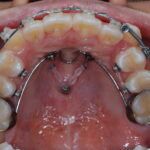

성장기 턱교정

성장기 아이들의 경우 유전적요인 또는 여러 조직의 기

능이상요인, 악습관등으로 인해 턱의 성장 및 치열의 발 육이 비정상적으로 나타날 수 있습니다. 무턱증이나 주걱턱, 비대칭등은 성장하면서 심한 얼굴의 변형이나 치열의 변형을 유발할수 있으므로 조기에 교정치료가 필요합니다.